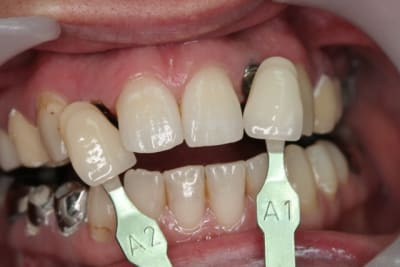

suite bis...

pose de l'implant pas simple en effet pour la 22...la corticale m'a en effet "guidé" beaucoup plus en palatin que ce que j'aurais voulu (cf pano...on à presque l'impression que je suis dans la 21...mais c'est une déformation "optique" les 2 implants ont en effet la même longueur...13mm)

photos de l'empreinte d'étude pour les autres couronnes...photos de la prise de teinte...

je sais qu'il y a une petite différence de hauteur de collet...mais les implants étant pas mal enfouis (les vis de cicat font 3mm) une petite gingivoplastie s'impose pour la 12...

le gain en expansion n'est pas faramineux...mais quand même...

suite des photos après la pose...cette fin de mois...

comme le disait dentiste57...la gestion de ces agénésies est un véritable défi esthétique...